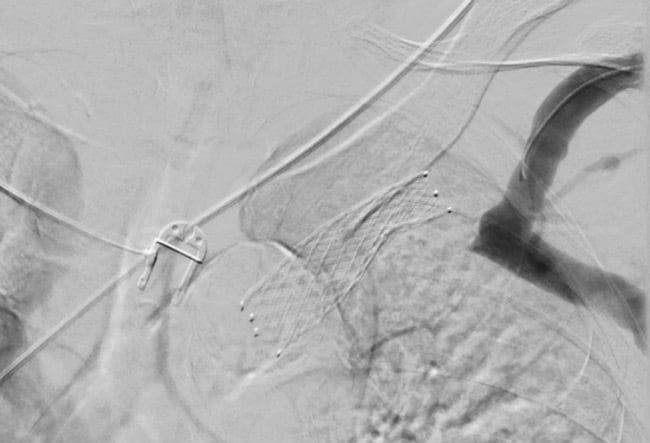

Pre-dilatation with a non-compliant balloon (7 x 80 mm) was performed.

A self-expanding 16 x 60 mm stent was advanced (9) and deployed with sufficient overlap with the previous one onto the cephalic vein.

Post-dilation was performed with a non-compliant balloon catheter (14 x 40 mm).

Final phlebography shows the correct placement of the stent (10) and the satisfactory patency of the treated segment.

At the end of the procedure, a good thrill of the AVF was achieved.